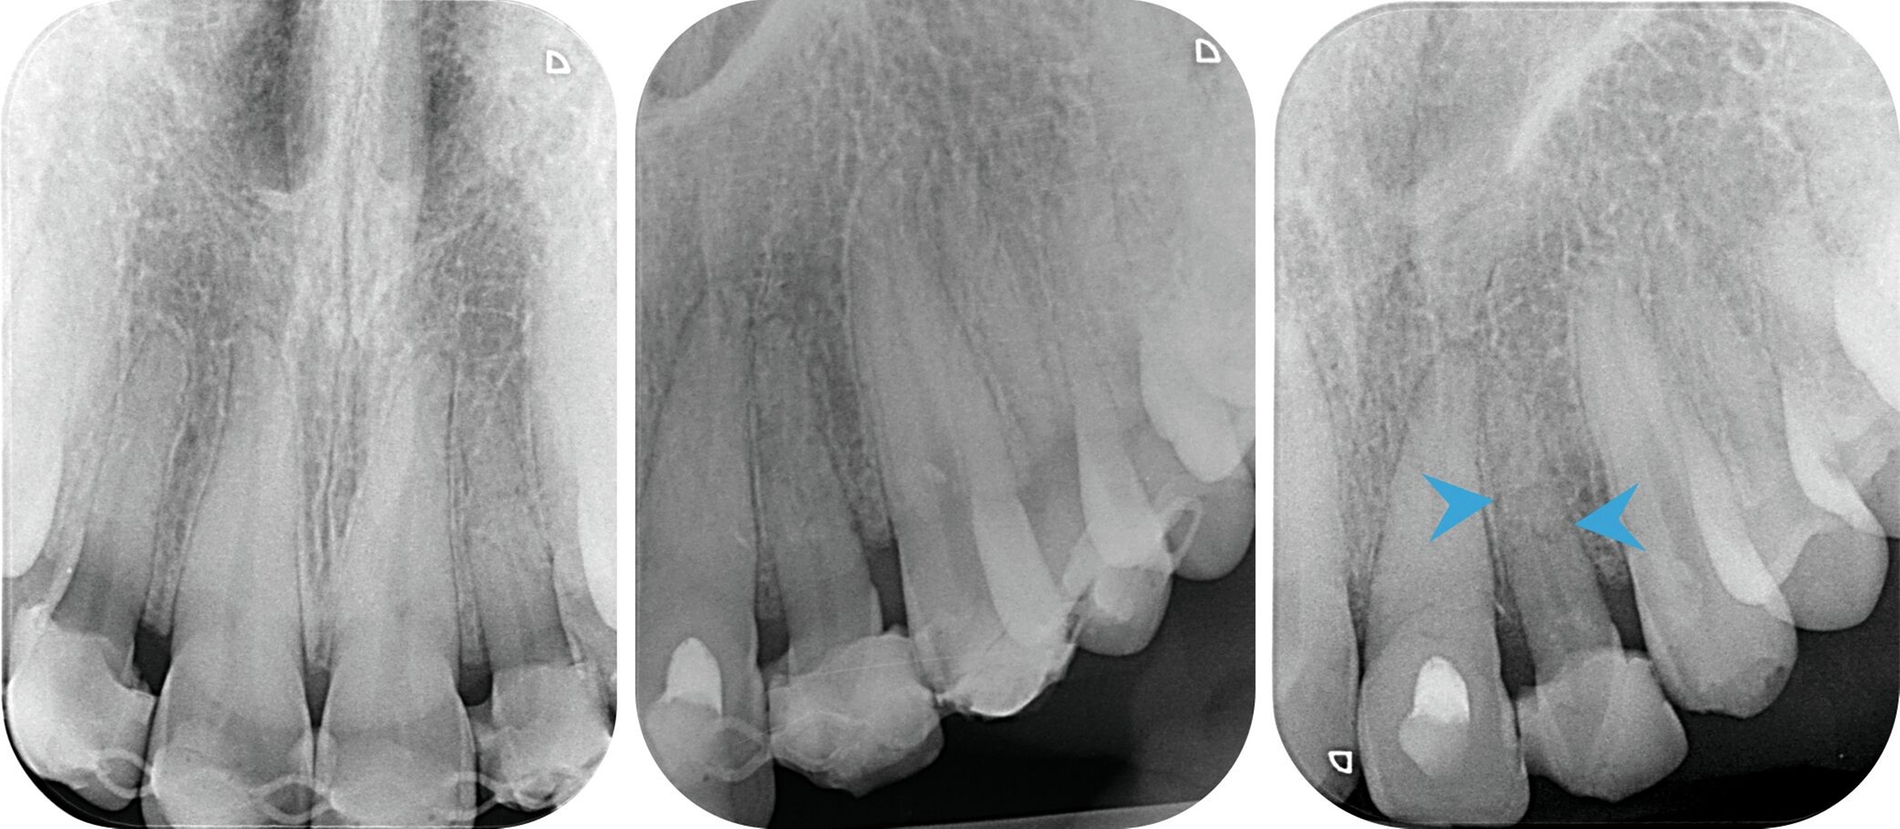

Bei der Nachkontrolle eine Woche später wurde ein Wechsel der medikamentösen Einlage zu Kalziumhydroxid im Zahn 21 durchgeführt. In regio 21 persistierte vestibulär eine offen granulierende Wunde. Zahn 22 reagierte weiterhin verzögert positiv auf die Sensibilitätstestung und durch eine Röntgenkontrollaufnahme ergab sich der Verdacht auf eine Wurzelfraktur (Abbildung 2B).

Nach sieben Wochen Schienungsdauer wurde der TTS schließlich entfernt. Zahn 21 zeigte sich klinisch gräulich verfärbt, reizfrei und mit Lockerungsgrad (LG) 0. Zahn 22 war weiterhin gelockert (LG II). In der aktuellen Röntgenkontrollaufnahme waren nun deutlich erkennbare Frakturspalte im mittleren Wurzeldrittel sichtbar (Abbildung 2C). Eine Kommunikation zur Mundhöhle konnte durch zirkuläre Sondierung des Sulkus ausgeschlossen werden und bei erneuter Sichtung des CT-Datensatzes konnte auf einen intraalveolären Verlauf der Fraktur geschlossen werden.

Im dargestellten Fall lag neben einer ausgeprägten Dislokation von Zahn 21 eine Wurzelfraktur von Zahn 22 vor. Solche intraalveolären Frakturen erfordern eine differenzierte Beurteilung. Der Behandlungserfolg hängt von der Lage des Frakturspalts in Relation zum gingivalen Sulkus ab und davon, ob eine Kommunikation zur Mundhöhle besteht. Etwa 25 Prozent der betroffenen Zähne entwickeln eine Pulpanekrose [Abbott, 2019].

Die Schienungsdauer bei intraalveolären Wurzelfrakturen wird in der Leitlinie mit bis zu zwölf Wochen angegeben, abhängig von der Stabilität des Fragments [DGMKG und DGZMK, 2022]. Zwar birgt eine verlängerte Immobilisierung Risiken wie den Abbau der parodontalen Gewebe oder die knöcherne Ersatzresorption (Ankylose) [Andreasen et al., 2004], jedoch zeigen aktuelle Daten, dass eine Langzeitschienung in bestimmten Fällen sogar die Apposition von Hartgewebe im Frakturspalt fördern kann [Isaksson et al., 2021].